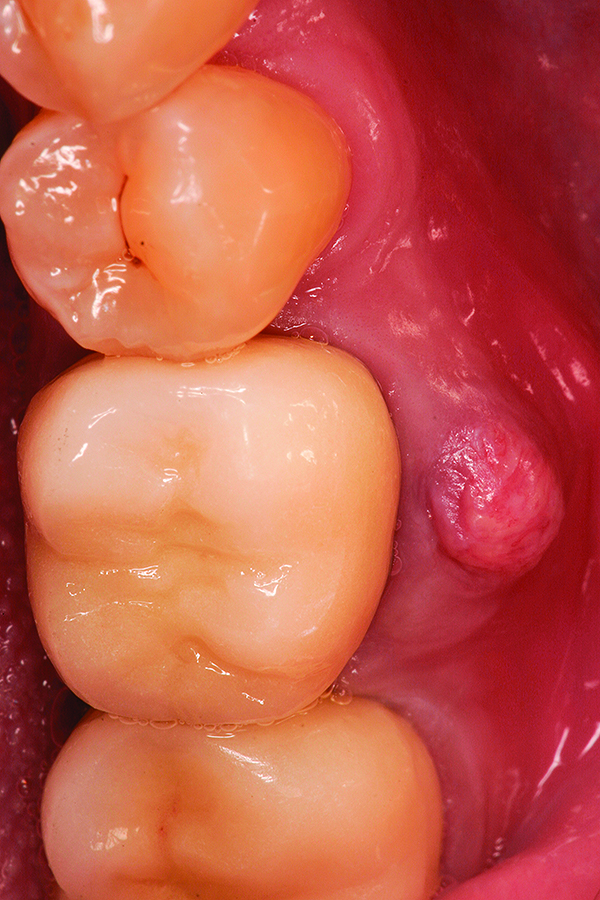

Fig 12. Note the significant formation of bone and repair of the buccal osseous defect at 3 months healing.

Figure 12

Fig 18. Surgical site at 3 months healing.

Figure 18